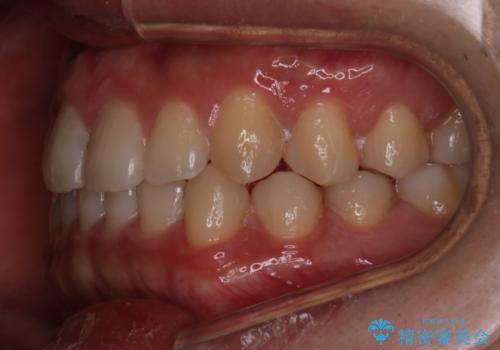

- 前歯のがたつきを主訴に来院されました。初診時、右上2番の口蓋側転位と右下7番の舌側傾斜が認められました。

インビザラインにてIPRと歯列弓拡大を行い、ゴム掛けで噛み合わせを改善する治療計画を立てました。

マウスピースの使用時間が短いため、シュミレーション通り進むか不安でしたが

治療期間1年で、主訴である前歯のがたつきを改善出来、

奥歯の噛み合わせも良くなりました。